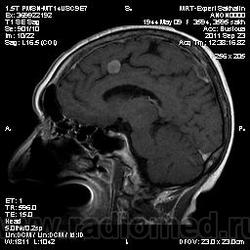

Рецидив менингиом?

В анамнезе удаление менингиомы в апреле 2011 года.Ранее также диагностировали  и оперировали менингиому-данных нет, у нас в первый раз.

Думаю операции были с двух сторон, веротно самых клинически значимых опухолей. Осталось ещё несколько. Неврином слухов нервов вроде нет. Но я бы на всякий случай и весь позоночный канал посмотрел на предмет опухолей. Так что это не рецидив. Особенно учитыаая обызвествление опухоли в затылочной области справа.

Кистозно-глиозные после удаления менингиомы.Атрофические изменения правого гиппокампа.

Получается менингоматоз ? А что в мосту ?

Получается.В мосту-наверное, очаг глиоза?

Валентин Львович, написала  про 2 менингиомы в правой затылочной области и  серпа  парасагиттально слева, описала кистозно -глиозные  изменения  в левой височной области после удаления менингиом+отметила глиоз в мосту, атрофические  изменения в правом гиппокампе.